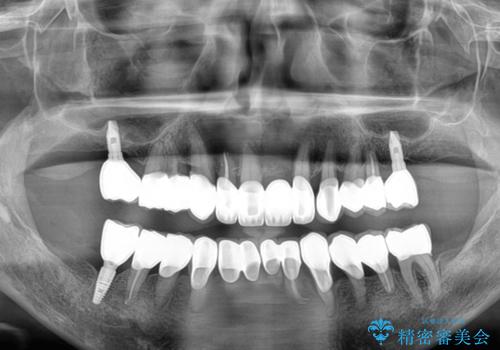

歯周病でグラグラの歯 矯正治療と歯周外科を併用した総合歯科治療

2~3年は早く終了する予定でしたが、途中で体調を崩されて来院されない時期が続いたため、非常に長期間の治療となりました。

上顎口蓋からの堅い歯肉を移植する角化歯肉移植術を行いたかったのですが、体調不良から実施しなかったため、最終補綴物であるオールセラミッククラウンを装着した後に、知覚過敏や境目が見てしまうといった問題が一部で発生いたしました。

最終的には痛みや違和感のない状態にて治療を終えることができました。